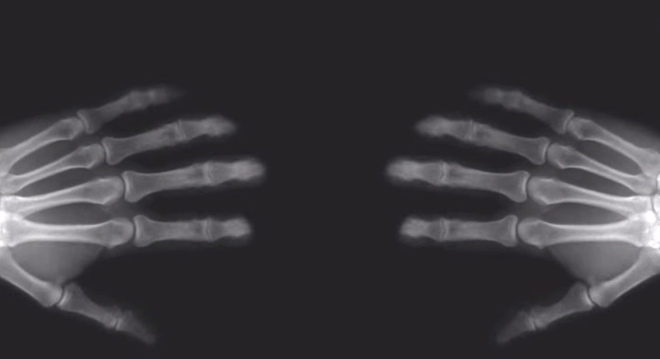

Old  Default Đây là thực tế những gì xảy ra khi bạn bẻ khớp ngón tay

Hầu như tất cả chúng ta có thói quen cho bẻ các đốt ngón tay của mình, mà không biết rằng nó có hại gì cho các khớp của chúng ta hay không.

Chúng ta cũng đã nghe rất nhiều lần về việc bẻ đốt ngón tay của chúng ta có thể nguy hiểm cho xương và chúng ta có thể bị viêm khớp vì việc này.